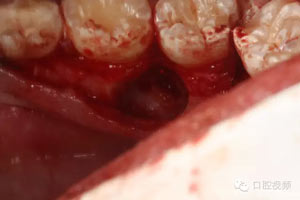

外科程序:

圖7.通過CBCT準(zhǔn)確定位,暴露35部分牙冠。

圖8.繼續(xù)去骨、暴露整個35牙冠。注意牽拉力度。